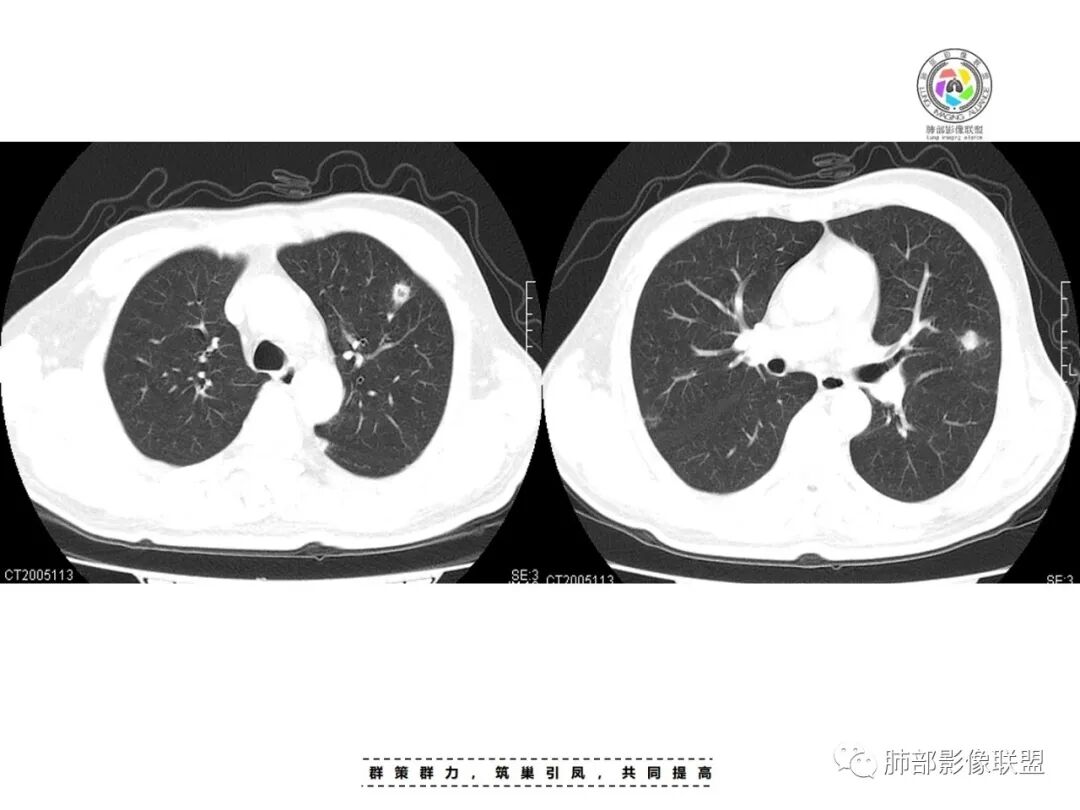

俞丽:患者男性,糖尿病,两肺多发结节,部分伴空洞形成,经治疗后好转,首先考虑感染性病变,肺克可能性大穿越七海的风:糖尿病史,双肺多发结节、空洞,进展快,治疗后吸收,考虑SPE,肺克或金葡飞鹰行动:患者男性,糖尿病病史,CT可见双肺多发结节,多位于胸膜下,部分伴空洞形成,经治疗后好转,首先考虑感染性病变,金黄色葡萄球菌或肺克需要考虑,患者病灶分散,双肺病灶血道来源,肝脏未见病灶,金黄色葡萄球菌感染可能性大一些。

李:双肺多发结节,部分空洞,胸膜下为主,考虑血源性,治疗后好转,如果抗炎好转,考虑化脓菌栓,肺克或金葡,如激素治疗后考虑gpa亚东:双肺多发结节,部分见空洞,与血管关系紧密,考虑感染性病变,短期内变化快,糖尿病史,金葡,肺克?王秀仙:糖尿病基础上伴发的多发结节,部分空洞,四大金刚金毛结克,首选肺克琦遇:糖尿病四大金刚里按病史只有金葡和肺克符合,病灶特点,胸膜下为主,病灶偏少,有不干净空洞,肝功无异常,金葡可能性大!大雄:但是没有发热 小强:糖尿病史,胸膜下,6天空洞增大,金葡可能,肺克一般进展后有融合大片改变,这个没有,但是金葡临床症状更重,这个也看不出来崔少钢:中年男性,血糖控制不良,感染指标高。影像:双肺多发的结节、空洞,分布比较随机,考虑肺克。病变变化不够快,囊张力不够高,感觉不像金葡。大雄:血流感染的金葡 与肺克影像上有重叠,不一定好区分肺克炎性指标(PCT)可以高的更明显金葡血流感染一般有可追寻的来源,比如皮损,软组织脓肿,骨髓炎,心内膜炎等肺克一般是来源肠道,经门脉系统入肝,形成肉眼可见的肝脓肿或者不可见的隐匿性微脓肿,再经肝静脉回流→下腔静脉→右心→肺动脉→肺内播散张小兵:糖尿病基础,胸膜下多发结节伴空洞形成,这么大的空洞结节无播散,排除结核。肉芽肿性多血管炎,一般累及支气管,引起支气管狭窄,也可排除,倾向肺克,鉴别金葡。流心明智:男性,51岁,以咳嗽、咳痰、气喘3天。既往糖尿病10年。血常规wBC及中性比、CRP、PCT均升高。CT示:双肺多发结节、小斑片影,胸膜下多,大部分实性、部分伴空洞,大部分类圆形、部分呈楔形,部分病灶可见滋养血管征,治疗后逐渐吸收。考虑:感染性病变,SPE,金葡>肺克,鉴别隐球、TB等。

一、双肺多发结节或小片影,随机分布,而未见支气管壁增厚及支气管远端如树芽征等改变,提示病灶来源于血道;且肺内结节边缘模糊,常可排除转移(一般转移瘤边缘多较光整,患者常有恶性肿瘤病史,且呼吸道症状不明显或出现较迟);

影像表现:双侧结节,常伴空洞形成,最多见于肺外周和肺下野,结节的边界清晰或模糊;可伴有斑片状实变区;多表现为基底贴近胸膜的楔形实变影,其内密度均匀或不均匀,可形成空洞。

影像学多发、外围胸膜下分布,病灶易液化坏死,周围可见滋养血管征,可见肺气囊,有张力,易形成气胸和脓气胸。

影像学表现:a 气道来源分布,多在一侧上肺或双下肺后基底段,实变病灶无支气管充气征,实变外支气管壁增厚,病灶早期就可见坏死空洞,因渗出物粘稠密度较大,常叶间裂下坠,有膨胀感。b 血源性病灶位于胸膜下或沿支气管走形,病灶内见小空洞,易伴发肝脓肿。